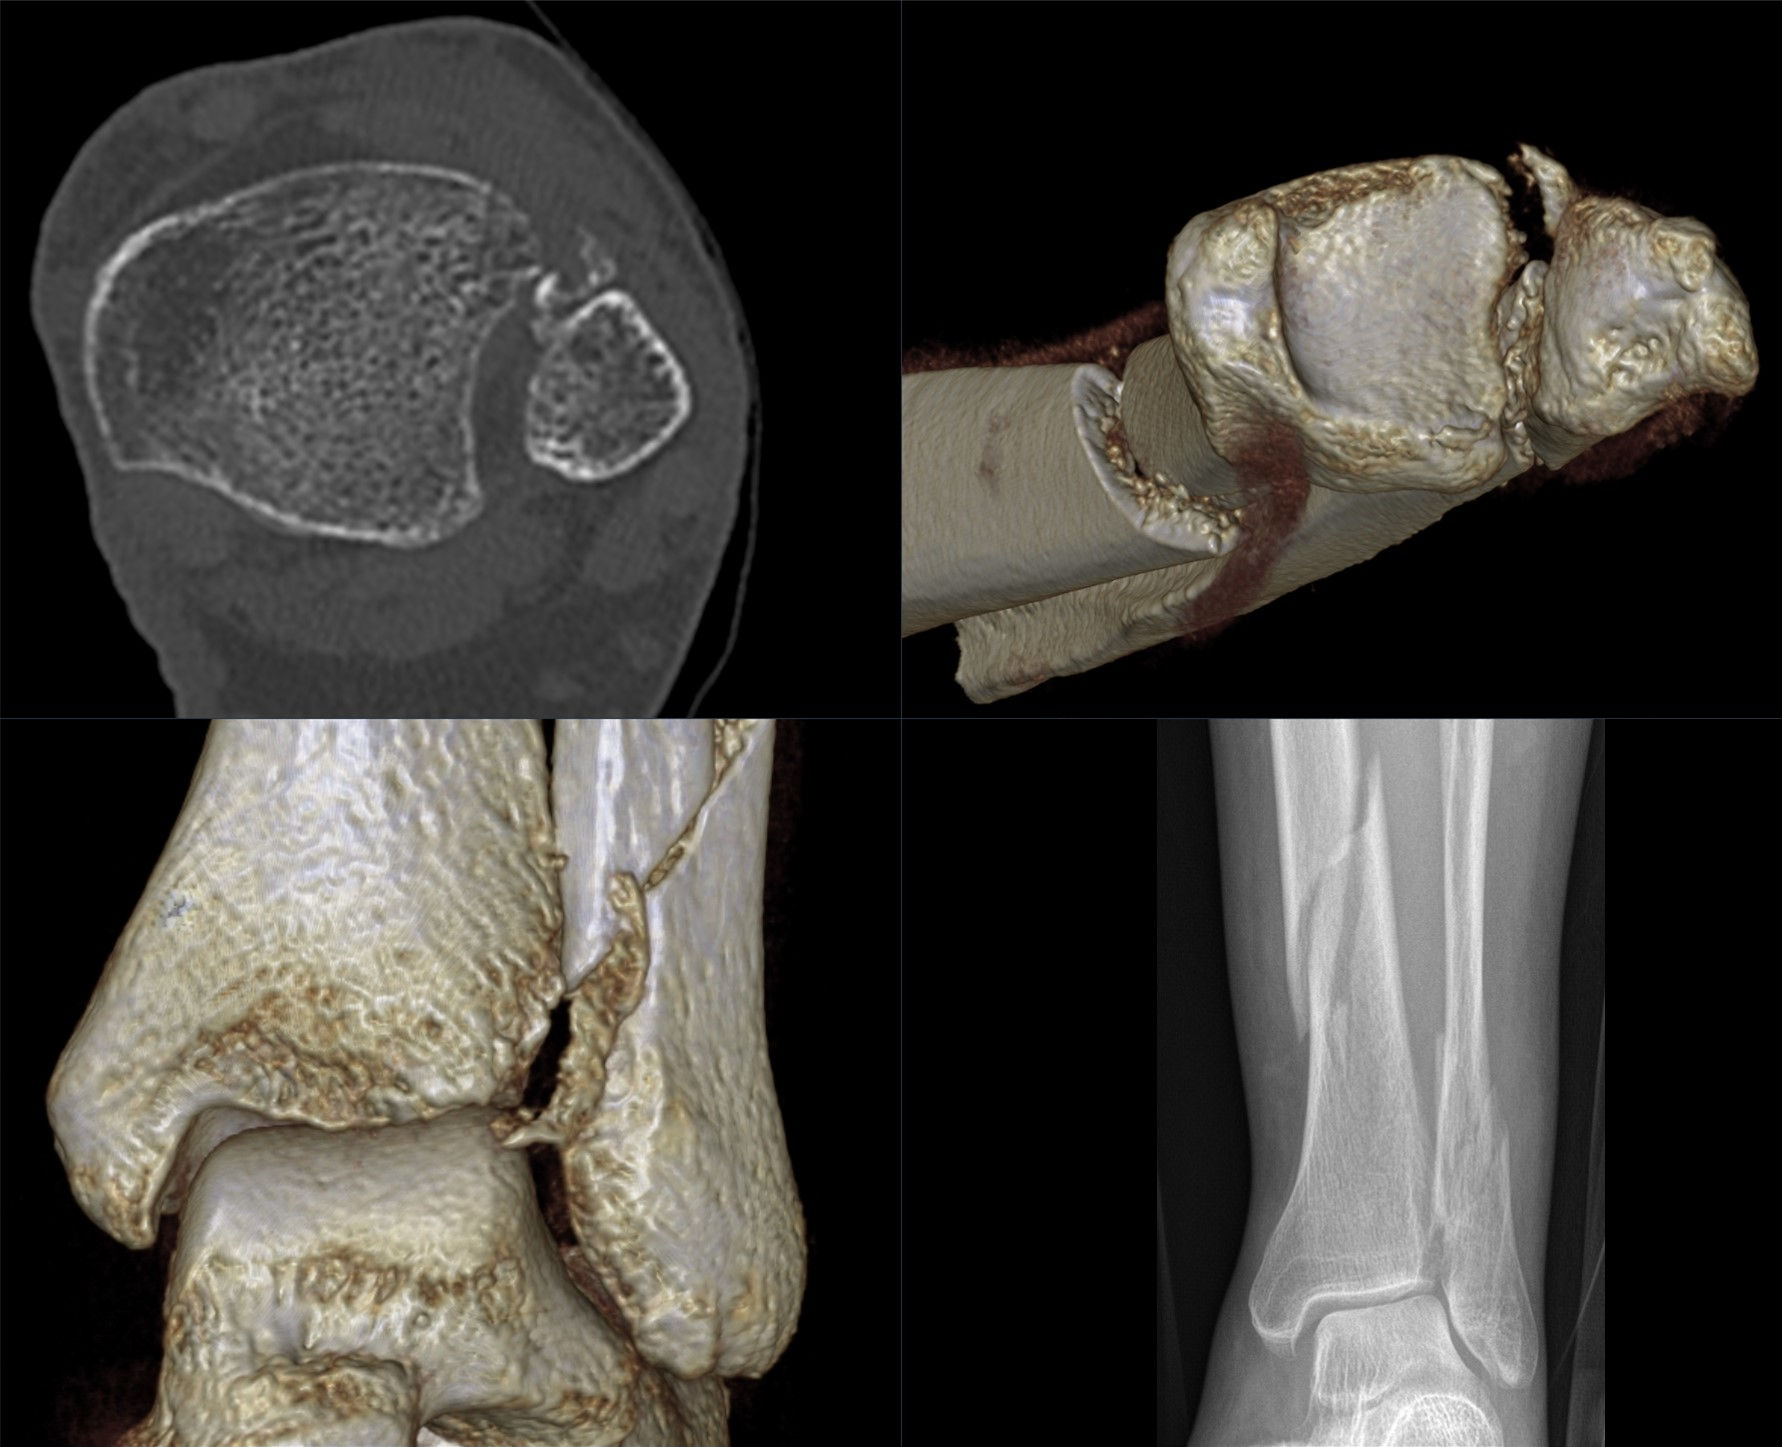

CT검사는 X선을 360도 방향에서 쏘아서 얻는 그림자 영상을 다시 재조합하여 3D형태로 얻을 수 있는 검사입니다.

CT는 보통 크게 두가지 목적을 위해 촬영하게 됩니다.

1) X-ray상 골절이 확실하지 않으나, 신체진찰상 골절이 강력하게 의심되는 경우 :

X-ray검사를 통해 모든 골절을 알아내면 정말 좋겠지만, X-ray 검사의 경우 뼈를 완전히 투과하지 못하는 X선을 쏴서 그 그림자를 얻는 방식이기에, 골절된 뼈가 그자리에서 벗어나지 않고 가만히 있는 경우에는 일부 X-ray 검사 만으로 골절을 확진하기 힘든 경우가 있습니다. 이는 1주 정도 시간을 두고 촬영하게 되면, 골절 부위에서 나오는 출혈로 인해 골절부위가 시간이 지나면서 벌어지게되는 것을 이용하여 확진을 할 수도 있는데요, 아무래도 요즘같은 흉흉한 시기에, 이런식으로 안내를 했다가는 'X-ray도 잘 못보는 의사' 나 '돌팔이'로 불리기 십상입니다. 그래서 신체진찰 소견상 위에 말씀드린 멍이 심하건, 발을 제대로 딛기 힘들다거나, 압통이 너무 심하다거나, 붓기가 너무 심하다거나 하는 경우에는, 애매한 X-ray소견이 있는 환자에서 한정적으로 CT검사를 권유하기도 합니다.

2) X-ray상 골절이 확실하고, 수술을 계획하는 경우

골절 수술은 일종의 퍼즐맞추기와 같다고 할 수 있습니다. 제자리에서 떨어져나간 뼈조각을 원래 위치에 맞추어 고정을 시켜야 하는 수술입니다. 이를 위해서 수술전에는 내가 어떠한 기구를 이용하여 어느 방향으로부터 진입해서 뼈조각을 고정할 지에 대한 계획을 하게되는데요, 이를 CT 검사를 통해 도움을 받을 수 있습니다. X-ray로도 할 수 있지만은, 앞서 말씀드린 것처럼 그림자만으로 계획을 했을 경우에 만약에라도 발생할 불상사를 예방하기 위해서라도, 좋은 수술 결과를 바란다면 CT검사를 하는 것이 좋습니다.